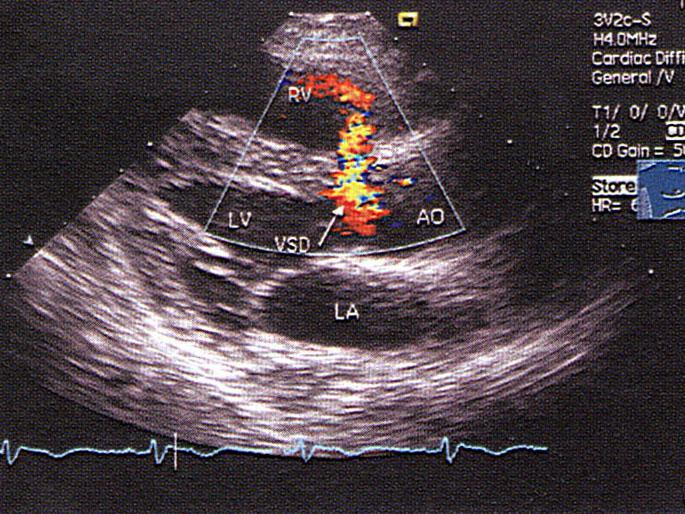

室间隔缺损,以上室间隔缺损属于哪型?(?)A.膜部室间隔B.干下型C.隔瓣下型D.肌型E.脊内型

问题 室间隔缺损,以上室间隔缺损属于哪型?(?)

选项 A.膜部室间隔 B.干下型 C.隔瓣下型 D.肌型 E.脊内型

答案 A